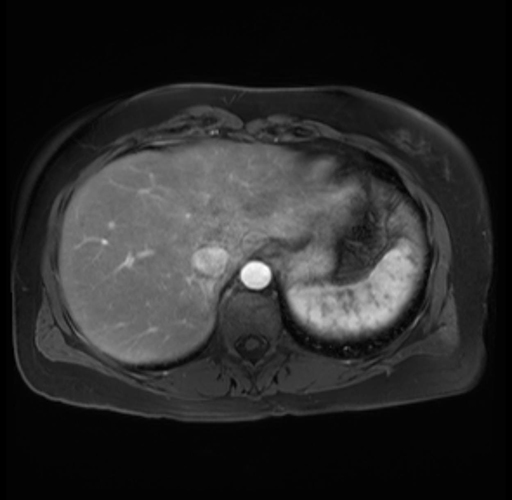

Imaging Analysis

Look through the patient's CT scan to identify any areas of concern for the necessary procedure.

Based on your CT findings, which issue(s) are present and would give reason for "planned slowing down moment(s)" in this case?

Considering a standard distal pancreatectomy procedure, what step(s) of the operation would you do differently in this case?